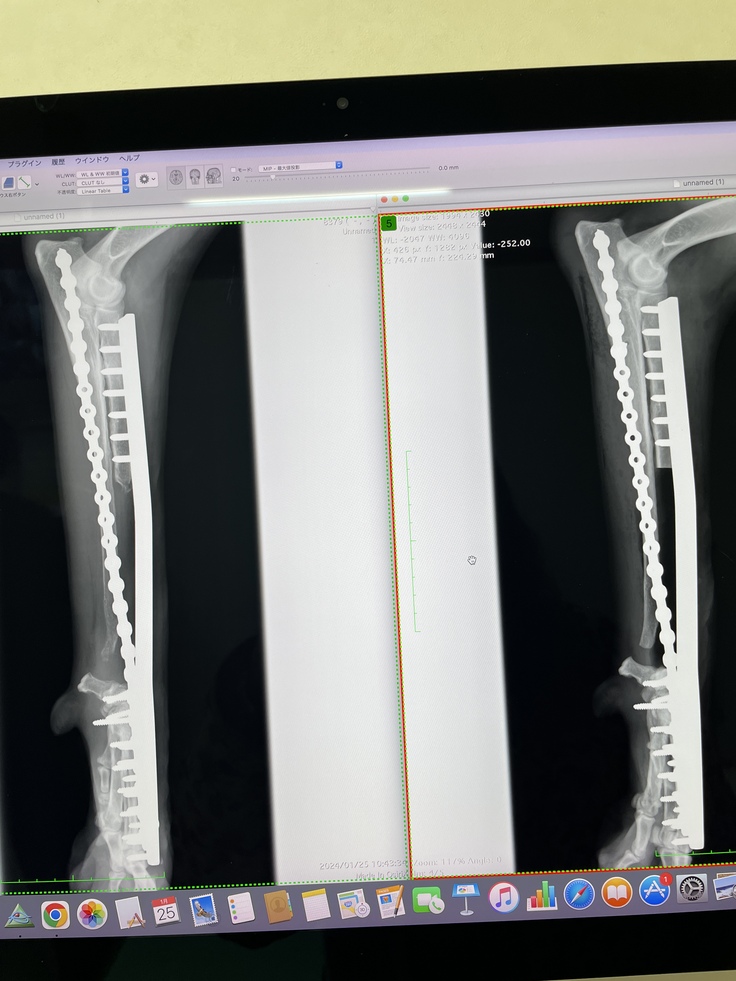

健診日でした!

今日は術後の定期検査の日でした!手と肺のレントゲンを撮ってもらいました☺︎3人がかりで鎮静剤無しでなんとかレントゲンを撮って頂けました✨費用もなるべく抑えて頂く努力をしてくださる病院の先生方に感謝です😢

モカも頑張ったね◎先生達にヨシヨシして貰ってご機嫌そうなモカでした♡肺の転移は初期とあまり変わらず、抗がん剤が上手く行ってるのかなと嬉しいお言葉を頂きました。このまま少しでも進行を緩やかにしていければいいなと思います。今回少し関節炎があるとの事で鎮痛剤の薬を貰いました。お薬増えちゃったけど頑張って飲もうね、モカ☺︎